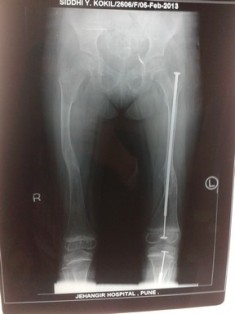

Surgical management: Children will have deformity of long bones because of bending and repeated fractures. Surgical correction of deformity and intramedullary rodding techniques can be used to correct the deformities and prevent refractures. Newer elongating rods are available which decreases the need for repeated surgery. After 18 years the risk of fractures decreases.